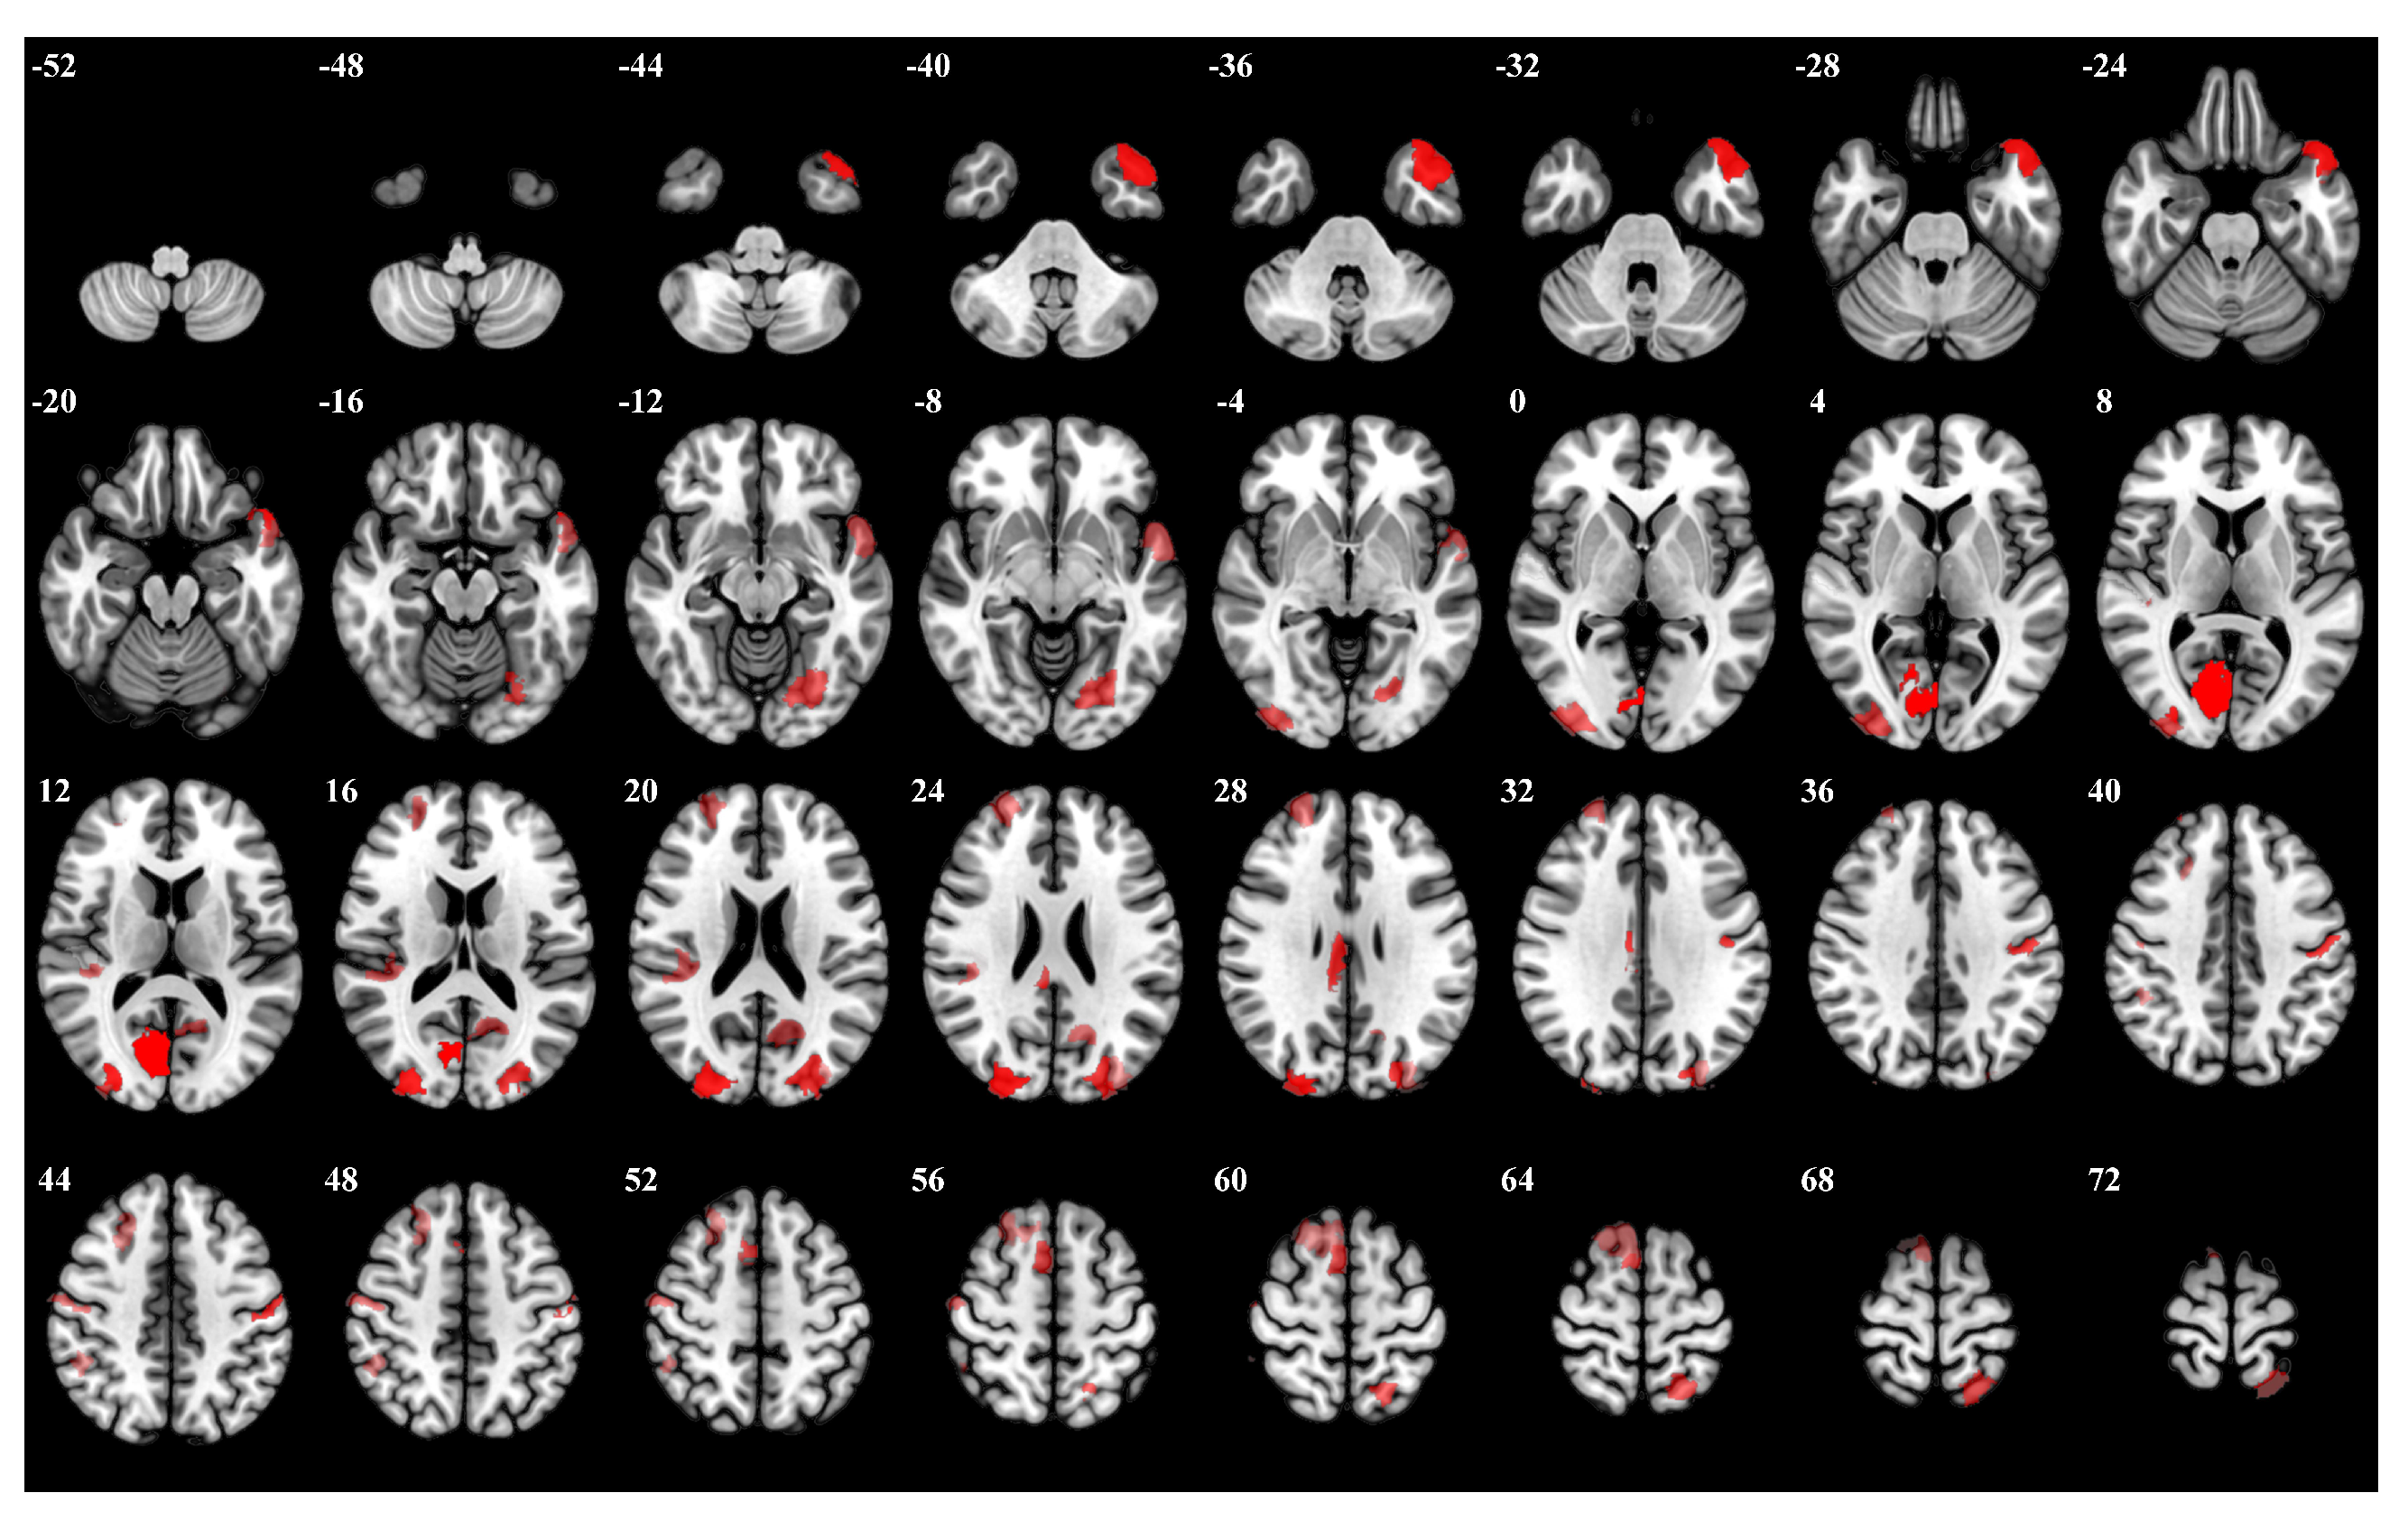

| Rank | Brain Regions | Side | Centroid Coordinates (R A S) | Importance Weight |

|---|---|---|---|---|

| 1 | Visual 19 | R | 9 −74 9 | 0.315 |

| 2 | Visual 26 | R | 27 −87 21 | 0.314 |

| 3 | Limbic Temporal Pole 6 | L | −40 −21 −27 | 0.274 |

| 4 | Visual 27 | L | −12 −71 20 | 0.272 |

| 5 | Somatomotor 17 | L | −51 −7 43 | 0.271 |

| 6 | Frontoparietal Control Cingulate 1 | R | 6 −26 28 | 0.253 |

| 7 | Salience Ventromedial Attention Medial 4 | R | 12 −34 43 | 0.247 |

| 8 | Visual 5 | L | −23 −73 −10 | 0.238 |

| 9 | Visual 18 | R | 35 −89 2 | 0.238 |

| 10 | Dorsal Attention Posterior 16 | L | −20 −57 66 | 0.234 |

| 11 | Somatomotor 21 | R | 52 −13 49 | 0.231 |

| 12 | Somatomotor 10 | R | 41 −29 18 | 0.228 |

| 13 | Frontoparietal Control Lateral Prefrontal Cortex 8 | R | 48 18 23 | 0.228 |

| 14 | Default Temporal 5 | L | −53 6 −11 | 0.226 |

| 15 | Default Precuneus Posterior Cingulate Cortex 2 | L | −13 −61 19 | 0.225 |

| 16 | Default Dorsal Prefrontal cortex an Medial Prefrontal Cortex 13 | R | 12 20 63 | 0.217 |

| 17 | Visual 28 | L | −32 −84 27 | 0.216 |

| 18 | Frontoparietal Control Parietal 5 | R | 54 −33 51 | 0.204 |

| 19 | Somatomotor 3 | R | 53 −14 6 | 0.203 |

| 20 | Default Dorsal Prefrontal cortex and Medial Prefrontal Cortex 12 | R | 12 −55 15 | 0.203 |